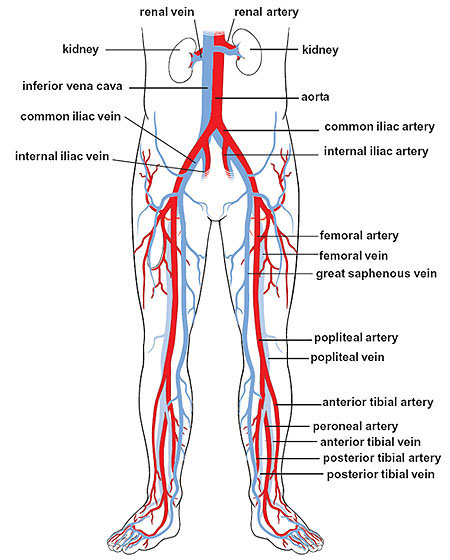

Deterioration in the knee area is a logical happening as we age. The

feet, legs and knees in particular are a complex mechanism that of course moves and flexes and being in the lower

extremities where a series of arteries, veins, nerves and lymph fluids and check

valves moving up the legs to rid the wastes that accumulate, have quite a chore

as we age. Therefore these areas easily become deficient in adequate

circulation (again blood, lymph and electrical) to have nutrition and

wastes handled efficiently in and out of the area. You have to be brain

dead if you look at that diagram to the left and not believe that circulation is

not going to play an important role in the health of your lower extremities.